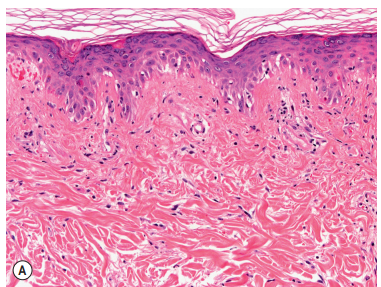

Lesional Biopsy:

Histopathology: Shows mild interface dermatitis with vacuolization of basal keratinocytes and sparse superficial lymphoid infiltrates.

Direct immunofluorescence may reveal granular deposits of IgG and/or IgM in lesions.